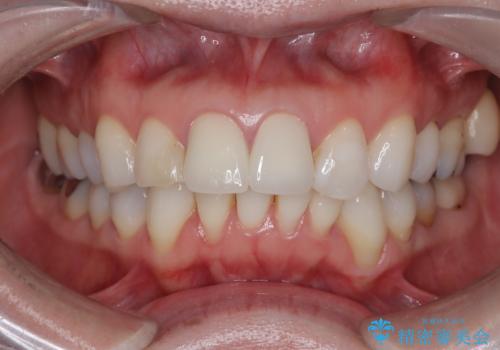

- [前歯の色が気になる」を主訴に来院された患者様です。歯の形を整えた後オールセラミッククラウンで治療を行いました。

以前他院にてセラミッククラウンを被せていたのですが、セメントの劣化なのか色が青白くなっていました。

歯の形を整えた後、色が透けないよう処置をしてオールセラミッククラウンで治療を行いました。